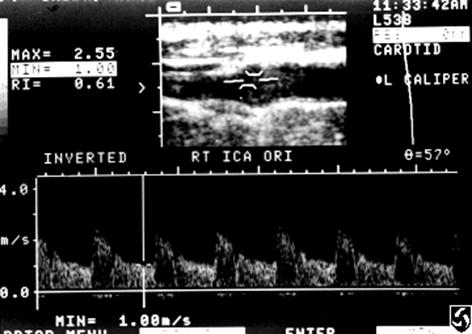

Explain the waveform of the ECA

high resistant

steep forward stroke

Forward flow during systole, low or reverse diastolic component